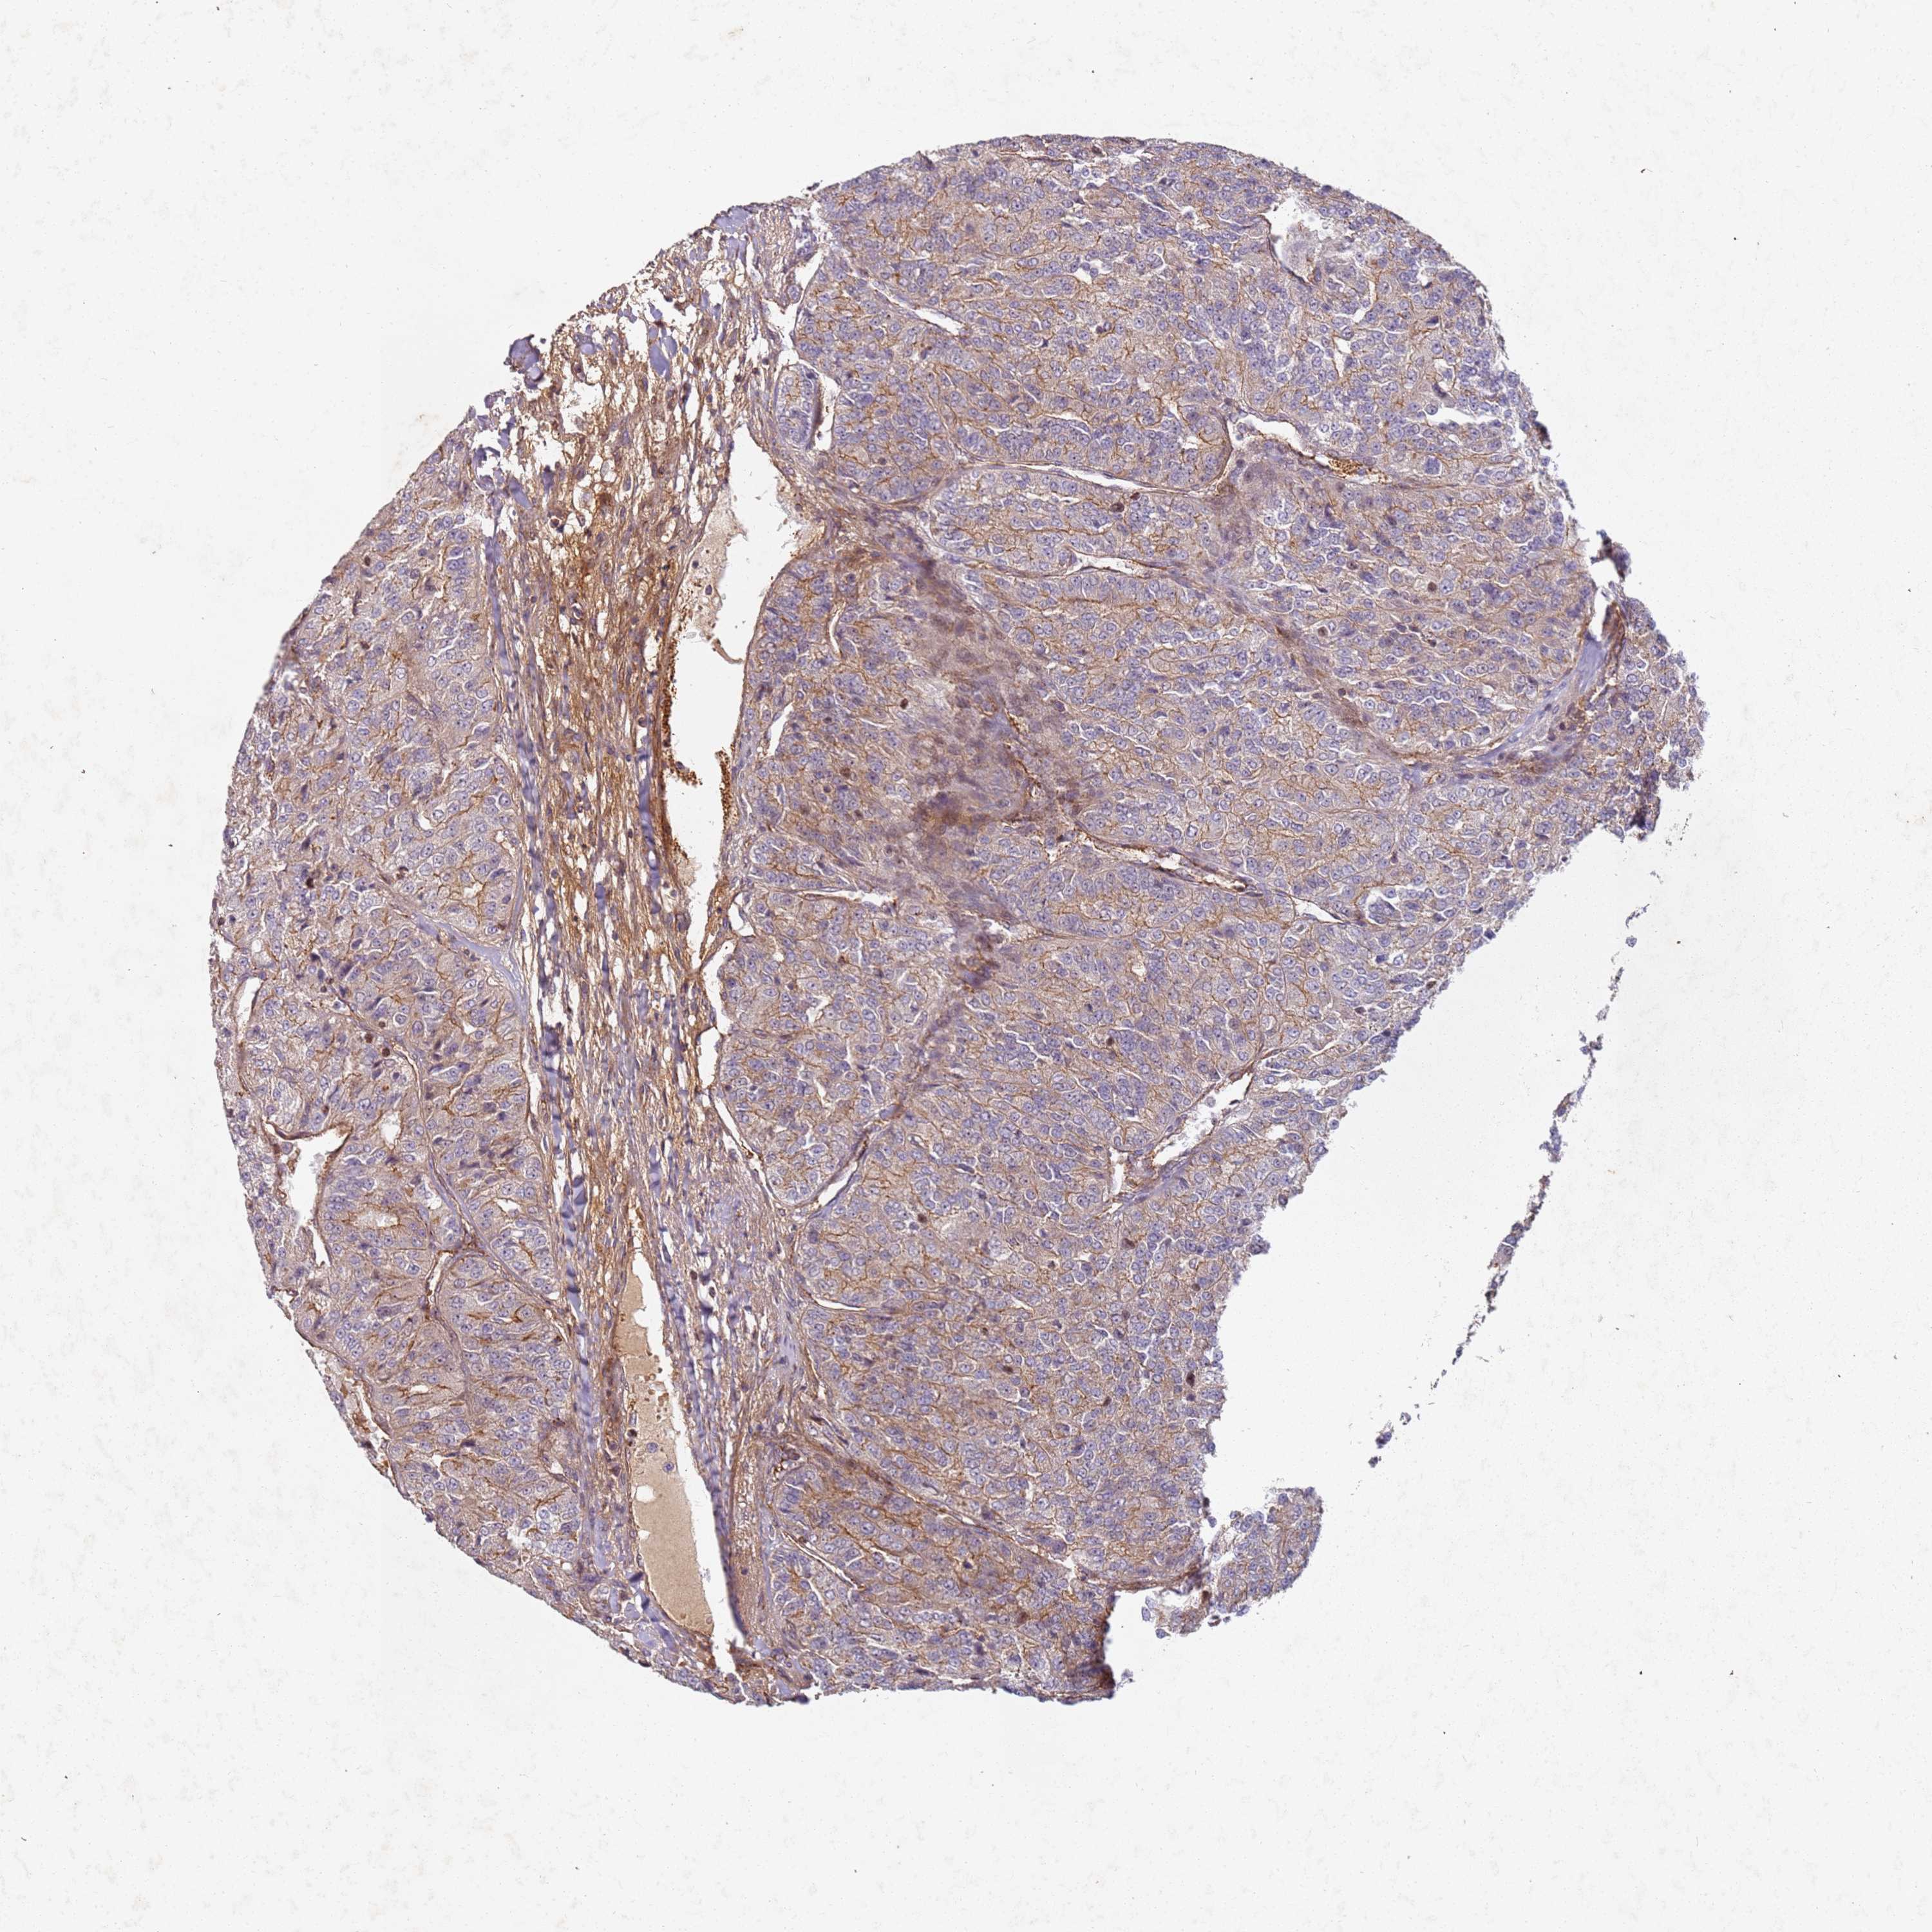

KIDNEY RENAL CLEAR CELL CARCINOMA (VALIDATION) - Interactive survival scatter ploti

The Survival Scatter plot shows the clinical status (i.e. dead or alive) for all individuals in the patient cohort, based on the same data that underlies the corresponding Kaplan-Meier plots. Patients that are alive at last time for follow-up are shown in blue and patients who have died during the study are shown in red.

The x-axis shows the expression levels (FPKM) of the investigated gene in the tumor tissue at the time of diagnosis. The y-axis shows the follow-up time after diagnosis (years). Both axes are complimented with kernel density curves demonstrating the data density over the axes. The top density plot shows the expression levels (FPKM) distribution among dead (red) and alive patients (blue). The right density plot shows the data density of the survived years of dead patients with high and low expression levels respectively, stratified using the cutoff indicated by the vertical dashed line through the Survival Scatter plot. This cutoff is automatically defined based on the FPKM cutoff that minimizes the p-score. The cutoff can be changed by dragging the vertical line or by entering a cutoff value in the square labeled "Current cut-off".

Under the Survival Scatter plot the p-score landscape (black curve; left axis) is shown together with dead median separation (red curve; right axis). Dead median separation is the difference in median mRNA expression between patients who have died with high and low expression, respectively. It is calculated as follows: median FPKM expression of dead patients with high expression - median FPKM expression of dead patients with low expression. This is intended to aid the user in visually exploring custom cutoffs and the associated p-scores and dead median separation.

Individual patient data is displayed and can be filtered by clicking on one or more of the category buttons on the top of the page. Categories describing expression level and patient information include: high, low, alive, dead, female, male and tumor stages. The scale of the x-axis can be toggled between linear and log-scale by clicking on the "x log" button. Mouse-over function shows TCGA ID, patient information and mRNA expression (FPKM) for each patient.

& Survival analysisi

Kaplan-Meier plots summarize results from analysis of correlation between mRNA expression level and patient survival. Patients were divided based on level of expression into one of the two groups "low" (under cut off) or "high" (over cut off). X-axis shows time for survival (years) and y-axis shows the probability of survival, where 1.0 corresponds to 100 percent.

C2CD4B is not prognostic in Kidney Renal Clear Cell Carcinoma (validation)

Best expression cut offi

: 0.4

P scorei

N/A

Average pTPM 4.5

Number of samples 100